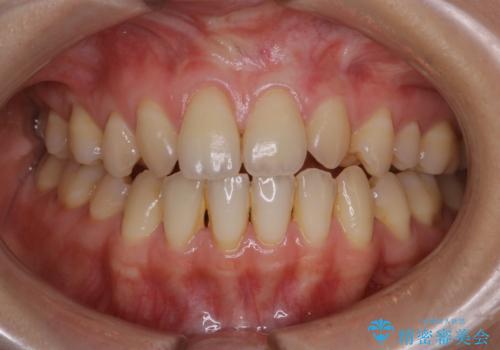

office-whitening(エクセレント)

治療症例の内容

- 20代女性

- 1日

- 1回

- なるべく1回で白くしたいとのことで来院されました。効果をより高めるために処置前クリーニング(¥3300)を行ってから、オフィスホワイトニングのエクセレントコース(¥29700)を行いました。

- ¥33000費用は治療当時の料金となります